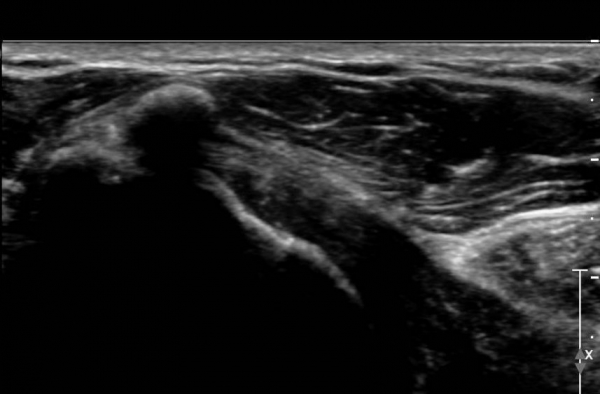

°ß°©ÇÏ±Ù°Ç Á¾´Ü¸é°Ë»ç(»çÁø 2)¿Í ȸ´Ü¸é°Ë»ç(»çÁø 2)¿¡¼­ ÈĹæÀ½¿µÀ» º¸ÀÌ´Â °í¿¡ÄÚ ¼®È¸°¡

°üÂûµÈ´Ù. Åë»óÀûÀÎ °ß°©ÇÏ±Ù°Ç Á¾´Ü¸é°Ë»ç¿¡¼­´Â °ß°©ÇÏ±Ù°Ç »óºÎ ¼®È¸È­·Î º¸ÀÌÁö¸¸ Ⱦ´Ü¸é°Ë»ç·Î

º¼ ¶§ °ß°©ÇÏ±Ù°Ç ÇϺο¡ ¹ß»ýÇÑ ¼®È¸ÀÓÀ» ¾Ë ¼ö ÀÖ´Ù.